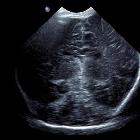

semi-lobar holoprosencephaly

Semilobar holoprosencephaly is a subtype of holoprosencephaly characterized by incomplete forebrain division. It is intermediate in severity, being worse than lobar holoprosencephaly and better than alobar holoprosencephaly.

As will most cerebral structural congenital abnormalities, semilobar holoprosencephaly is visible on all modalities, but in general is identified on antenatal ultrasound, and best characterized by MRI.

The basic structure of the cerebral lobes are present, but are fused most commonly anteriorly and at the thalami and there is partial diverticulation of brain (dorsal cyst). Features include :

- absence of septum pellucidum

- monoventricle with partially developed occipital and temporal horns

- rudimentary falx cerebri: absent anteriorly

- incompletely formed interhemispheric fissure

- partial or complete fusion of the thalami

- absent olfactory tracts and bulbs

- agenesis or hypoplasia of the corpus callosum

- incomplete hippocampal formation

An easier approach might be to assess fusion of more than 50% of the frontal lobes which might be suggestive of semilobar holoprosencephaly .